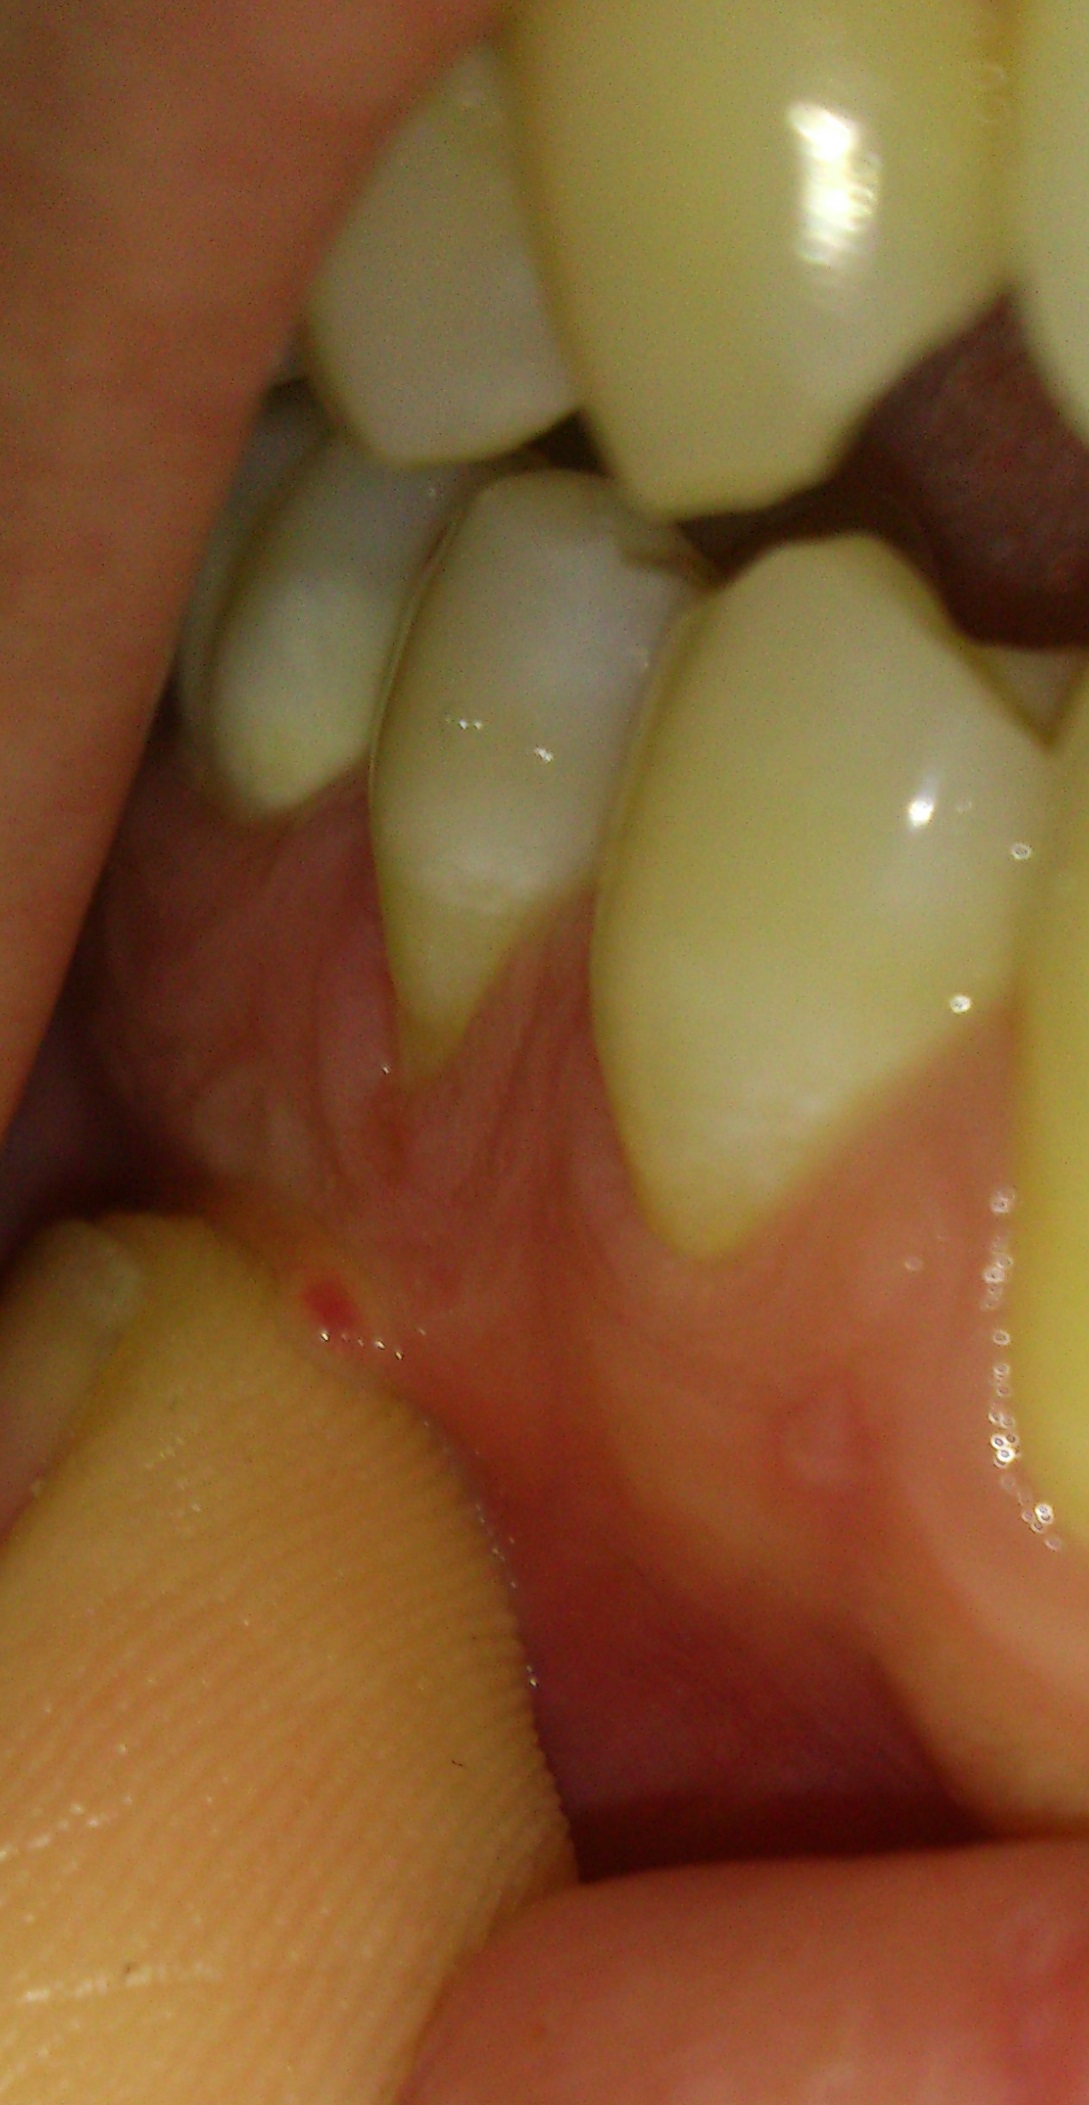

Salve, in seguito a un rapporto orale non protetto ho iniziato ad accusare alcuni disturbi ma mi soffermo a quelli dell'apparato orale: Ho la lingua bianca ormai da 4 mesi e al test dei miceti risulto negativo, ho avuto dolori all'altezza delle mole del giudizio che sono coricate ma a destra una è uscita per metà "storta". Nell'ultimo periodo ho notato una carie tra premolare e molare inferiore dx che ho fatto curare e nella gengiva del premolare c'è una strana pretuberanza.. Capisco che nn ci si possa basare su delle foto e che un consulto online non può essere preciso, ma mi farebbe piacere ricevere un parere, il mio timore è che si tratti di hpv..

Caro Signor Filippo, certo bisogna fare una visita clinica da un patologo orale prima e da un Medico specialista in Medicina interna poi per fare anche visita, anamnesi e analisi ematologiche mirate ai sospetti diagnostici che emergessero, per fare una diagnosi differenziale, sia in sede orale che sistemico! Le foto in se stesse mostrano solo macule da glossite ed archi palatini ed ugula e faringe in flogosi accentuata. Inoltre nella foto che mostra il fornice in corrispondenza dei due premolari inferiori si nota una formazione bollosa cerchiata da una anello di flogosi, tipo aftiforme e segnata dal pollice la formazione che in realtà potrebbe essere la più tranquilla o la più pericolosa, come si può dire da una foto, senza palpazione, visita clinica etc e per di più da una foto non macro? Capisco la sua apprensione ma proprio per questo si faccia visitare da un patologo orale e da un internista che sappia valutare tutte le analisi mediche ematologiche! Solo così potrà sapere cosa ha e farlo curare!questa lesione va differenziata da verruche, condilomi papillomi in particolare. Pretendere una diagnosi stomatologica da una sommaria descrizione soggettiva di una lesione è veramente cosa "curiosa" oltre che sbagliata e pericolosa! Sappia che per esempio, il virus del Papilloma umano, HPV (Human Papilloma Virus) ha predilezione per le mucose genitali ed orali e per gli epiteli squamosi. Nella mucosa orale, il papilloma, si manifesta in tre varianti istopatologiche: Squamoso, verruca vulgaris (molto meno frequente) e Condiloma accuminato. Bisogna fare attenti esami sullo stato del suo sistema immunitario e attuare una "sorveglianza" preventiva e diagnostica perchè se ne possono formare altri. Il medico più adatto a questa sorveglianza è lo Stomatologo, il Patologo Orale, il Dermatologo o il Virologo o l'Immunologo o il Clinico Medico! Sarebbe importante anche avere un esame istologico su quelli tolti! Si rimane contagiosi fino a dopo l'ultimo di almeno due o tre controlli nel tempo di due mesi dall'ultima escissione. Aggiungo che si possono fare dei tamponi orali per la ricerca del virus HPV!Ne parli, ripeto, con un Dermatologo o gli altri specialisti consigliati! Il tampone lo può fare anche il suo Dentista se è organizzato per farli avere integri ad un laboratorio di istopatologia e virologia!Valutare poi la sua immunità cellulo mediata dai Linfociti T. Ed ancora, dopo l’introduzione della HAART (highly active antiretroviral therapy), si è visto che le lesioni da HPV anziché diminuire, sono aumentate (in sede orale e genitale) ed anche in relazione al calo della viremia a seguito della terapia antivirale. Però stia tranquillo, si risolve tutto e tornerà la normalità, sicuramente e senza problemi, sia quindi molto sereno!In ogni caso ho parlato di diverse possibilità diagnostiche che vanno differenziate e confermate, ovviamente. Lei chiede ed io devo rispondere!La Diagnosi differenziale è doverosa e non semplice a volte con lesioni traumatiche delle mucose orali, Herpes zoster gengivite necrotica Etc. Coraggio quindi si faccia visitare. Sono soldi spesi bene, mi creda! Diffidi di chi non fa pagare la Visita! Che altro posso dirle!? Che ha una recessione gengivale in corrispondenza del secondo premolare della foto con una insufficienza di gengiva aderente dato che è compromessa la linea di giunzione mucogengivale! Si faccia visitare anche da un Dentista Parodontologo! Cordialmente Gustavo Petti, Parodontologia, Implantologia, Gnatologia e Riabilitazione Orale Completa in Casi Clinici Complessi ed Ortodonzia e Pedodonzia la figlia Claudia Petti, in Cagliari.

La protuberanza sembra una fistola, dente in necrosi. La "mola" del giudizio probabilmente estratta. Dalla foto la lingua non sembra così bianca... la spazzola mai? La coltura per miceti non è così semplice la faccia ripetere. Gli altri sintomi sui quali passa sopra quali sono? Cordialità V.